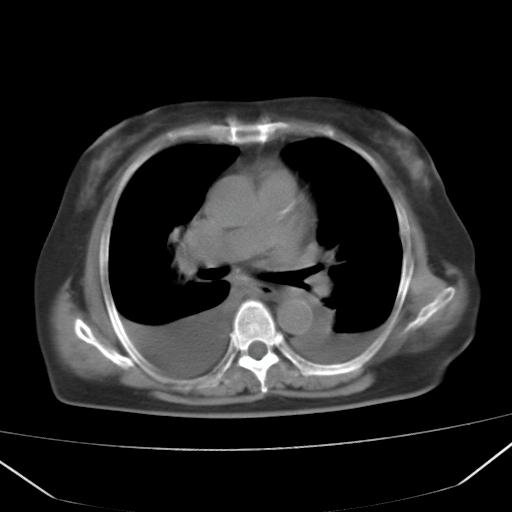

以下是引用liuyue在2008-4-19 22:25:00的发言:[br]先考虑:1.心衰伴肺水肿、双侧胸腔积液、叶间积液、双下肺不完全性肺不张; [br] 2.冠状动脉粥样硬化。

以下是引用lijuanln在2008-4-19 23:05:00的发言:[br]两侧胸腔积液,肺水肿[br]心包积液[br]提示心衰

以下是引用jiangjing在2008-4-20 10:43:00的发言:[br]结合病史支持 冠心病[冠状动脉钙化],心功能不全,肺淤血、肺水肿,双侧胸腔与斜裂积液